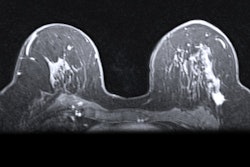

Although advocates of contrast mammography won some converts, breast MRI was still preferred as the main breast cancer screening option for intermediate-risk women in a debate on 2 March between advocates of the two technologies at the ECR Overture.

Breast MRI and contrast-enhanced mammography have been explored in recent years to detect and diagnose breast cancer as an alternative to conventional mammography for intermediate-risk women. However, there is no consensus among researchers as to which technique is superior. This ongoing debate netted a 2022 EuroMinnie award for being the most significant news event in European radiology.